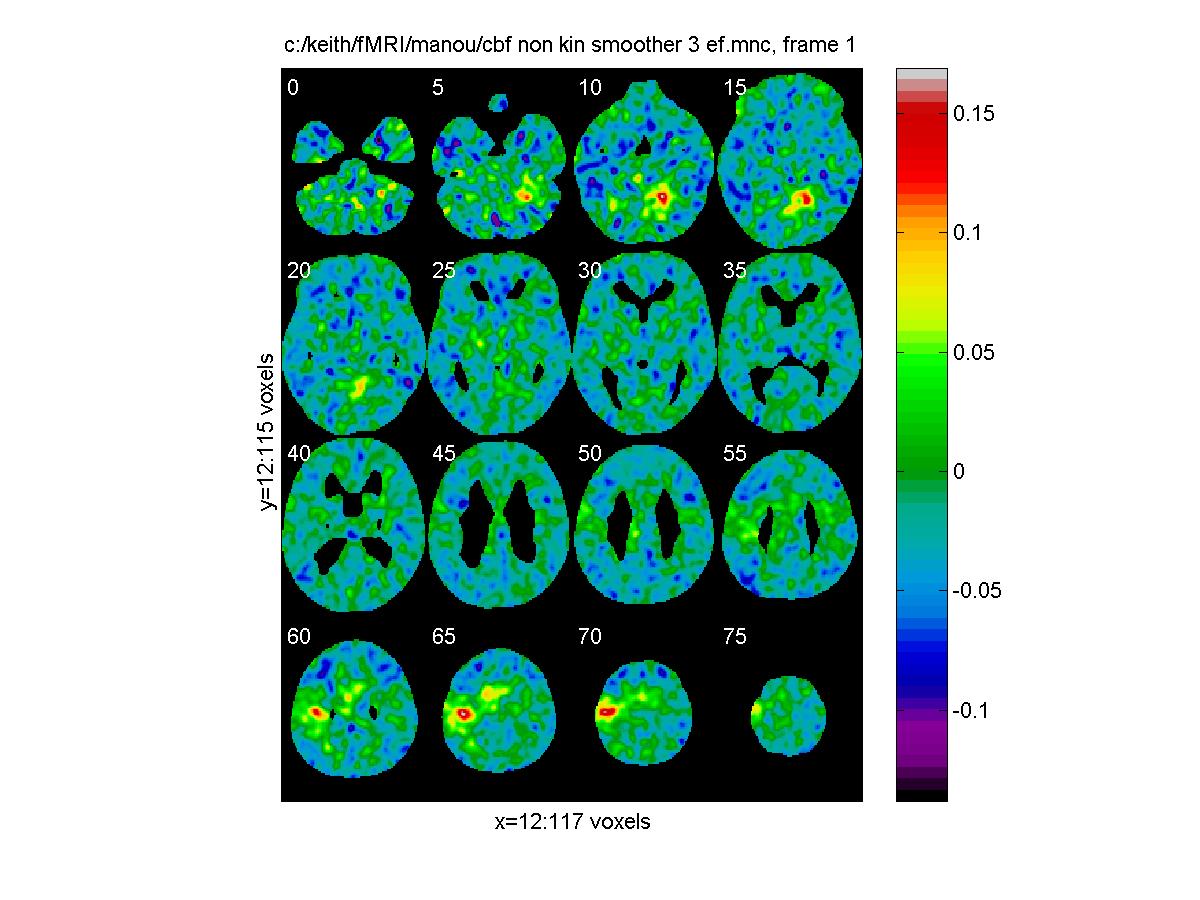

To look at the results, we can choose the overall average effect as a mask, which we can threshold at say 0.65 (half its maximum). Then we can again use view_slices to take a look at every 5th slice through the volume of say task 3. For the effect of task 3 - baseline (in units of normalized cbf):

mask='c:/keith/fMRI/manou/cbf_non_kin_smoother_0_ef.mnc'

clf;

view_slices('c:/keith/fMRI/manou/cbf_non_kin_smoother_3_ef.mnc',mask,0.65,[0:5:79])

![[Click to enlarge image]](figs_pet_tn/fignormef.jpg)